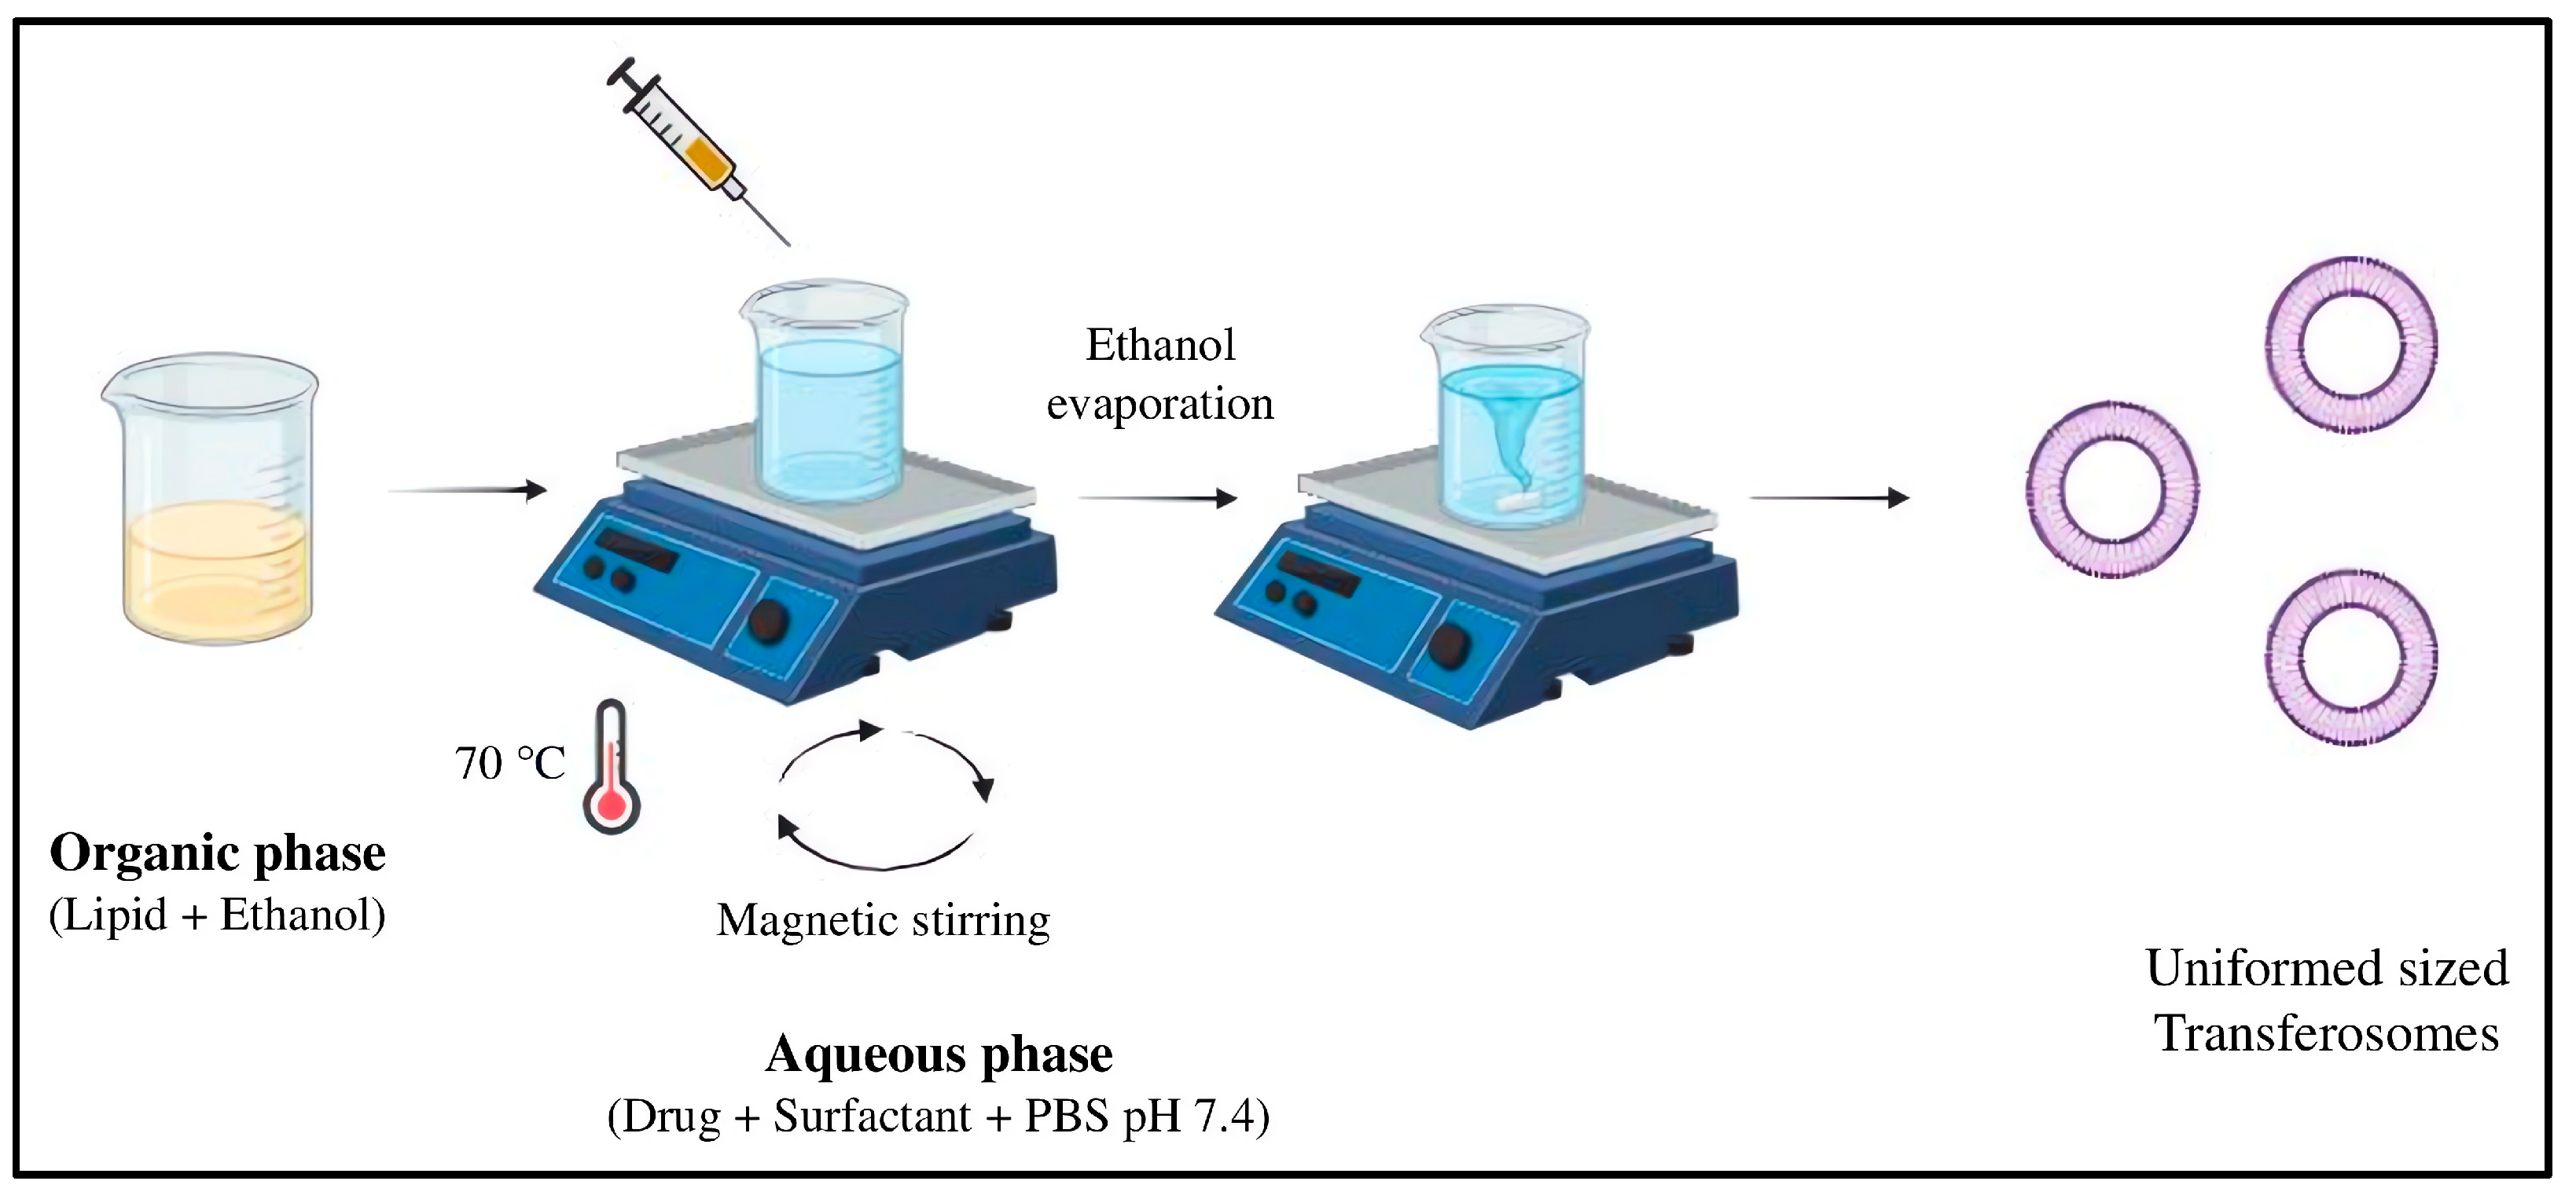

3.2.1. Preparation and Characterization of MTX-Loaded Transferosomes